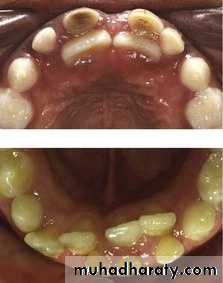

8-Dental caries

Dental caries Dental caries should be considered as one of the local factors causing mal occlusion. Caries which leads to premature loss of a deciduous or permanent tooth may cause drifting,axial inclination, over eruption.